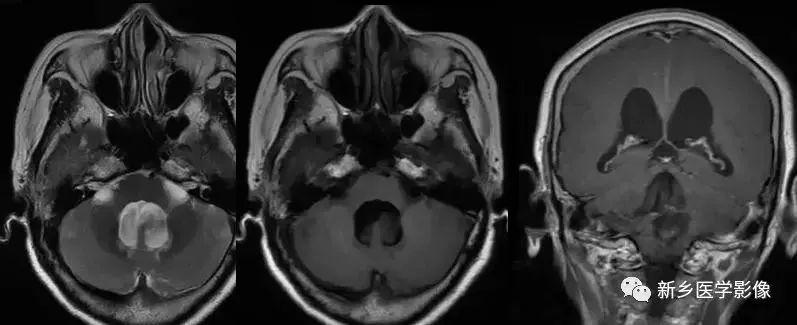

4.Dandy-Walker’s综合症

又称第四脑室中侧孔先天性闭锁。在胚胎早期期,第四脑室正中孔及侧孔闭寒,导致四脑室呈囊性扩张,并伴有小脑蚓部及半球发育不良,扩张之四脑室向后发展,并与枕大池相连,使后颅窝扩大,小脑幕抬高。本病出现脑积水通常见于婴儿期,或者出生后即存在,但到成人期才发病。